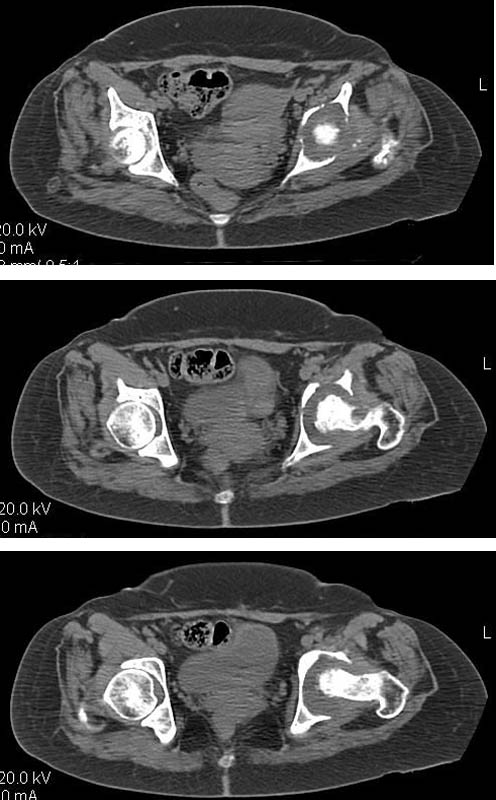

Дополнение - проконсультировался с женой-она специалист рентгенолог - на КТ большое колиество мягкотканного компонента - ищите микоплазмы или бруцеллу. Я склоняюсь к виопсии.

Пртезирование через пол года после коксита закончившегося лизисом сустава, который на снимках выглядит как гнойный? Что значит неизвестной этиологии?

Уважаемый коллега! Последняя версия - мы пролистали ренгенологическую книженцию-так картинка вполне подходит под сустав Шарко (neuropatic joint ). В тазобедренном суставе патология редкая (но меткая). Ищите причину - варианты - нейросифилис, сирингомиелия, опухи спинного мозга (и выше тоже) компрессия спинного

мозга извне, рассеяный склероз, алкоголизм. А так-же : склеродерма ,Рейно,ревматоидный артрит, амилоидная инфильтрация нервов,и это не считая всяких менингеомиелоцеле,asymbolia,Riley-Day syndrom,и все возможные другие нейропатии. На данном этапе не спешите оперировать(протезирование протиопоказано при нейропатических суставах),проконсультируйтесь с классным невропатологом,сделайте МЯР головного озга и

весь позвоночник. И держите нас в курсе - случай крайне интересный :)